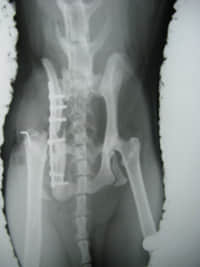

好不容易选了一块10孔钛金属骨板,一问价钱吓死人,1534元,另外每颗钛合金螺丝要90元,配齐一套要2000多块钱。有点郁闷,猫咪没有钱,只能摊大只如来神掌向主人要钱。主人赚钱也不容易啊。猫咪,早知今日,何必当初。

做了第一期手术,右侧股骨头切除假关节成型手术,右侧髂骨坐骨长骨板修补手术。起码解除了盆腔对直肠的压迫,可以拉大便